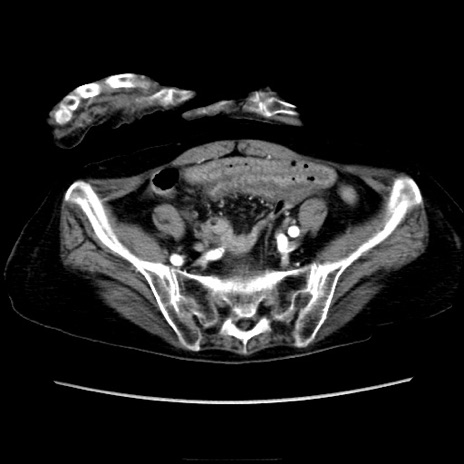

症例40(横断像)

【症例】90歳代女性

【主訴】腹痛・嘔吐

【現病歴】 食欲低下、嘔吐があり昨日他院受診。肺炎と診断され入院となる。入院後より腹部全体に圧痛あり。胃管留置され経過みていたが、症状持続するため、

当院転院となる。

【既往歴】胸椎圧迫骨折、胆石症

【身体所見】腹部:中央に激痛あり、圧痛あり、反跳痛不明

【データ】WBC 17100、CRP 18.82

横断像